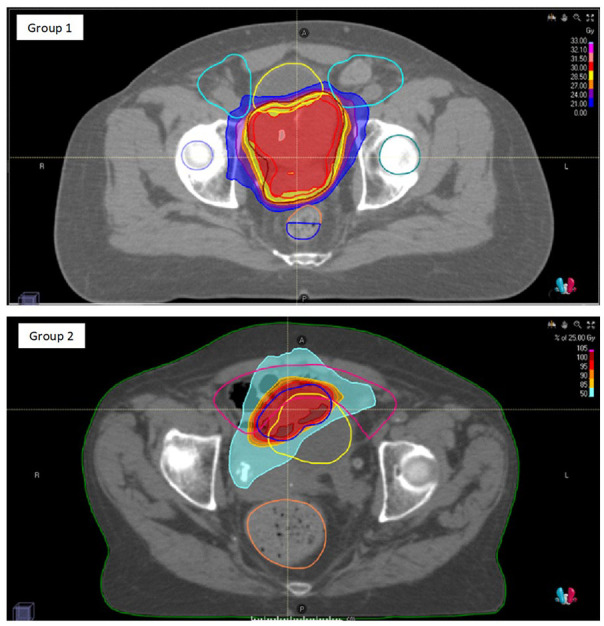

Methods: Patients who underwent hypofractionated radiotherapy to the gross disease or to the tumor bed after transurethral resection of bladder tumor from 2017 to 2021 at the European Institute of Oncology IRCCS, were retrospectively considered. Schedules of treatment were 30 and 25 Gy in 5 fractions (both every other day, and consecutive days). Treatment response was evaluated with radiological investigation and/or cystoscopy. Toxicity assessment was carried out according to RTOG/EORTC v2.0 criteria.

Abstract Image